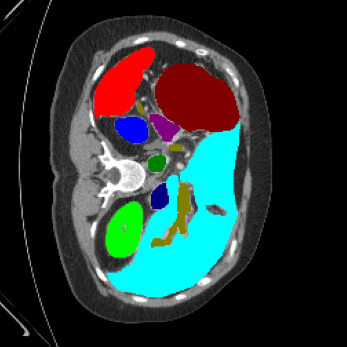

| Ground Truth | LoGoNet | DiNTS Search |

|---|---|---|

![]() |

We begin by qualitatively inspecting our model. Figure 3 compares the output of LoGoNet to the best performing baseline model in BTCV dataset, i.e., DiNTS Search (more qualitative comparisons can be found in appendix section 11). We see that our model particularly excels in segmenting organ boundaries. This can be attributed to our effective strategy for extracting local-range dependencies, which plays a crucial role in extracting details from input data. Our model’s adeptness in capturing long-range dependencies allows it to grasp contextual information that extends over significant distances within the data. Simultaneously, its proficiency in handling short-range dependencies ensures precision in capturing localized patterns.